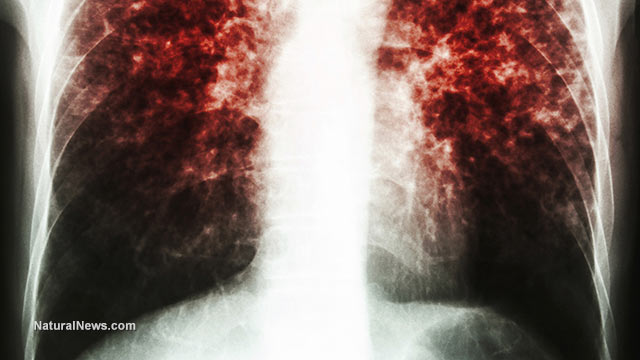

Government hiding unprecedented TB infection rates among relocated refugees

(NaturalNews) More Americans might be accepting of President Barack Obama’s zealous push to flood the country with refugees from war-torn parts of the world, if only he, along with federal and state officials, were more transparent about the entire process.Like for instance being… |